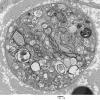

PERIPHERAL NEUROPATHY

4 AXONAL DEGENERATION

3 Electron Microscopy (2)